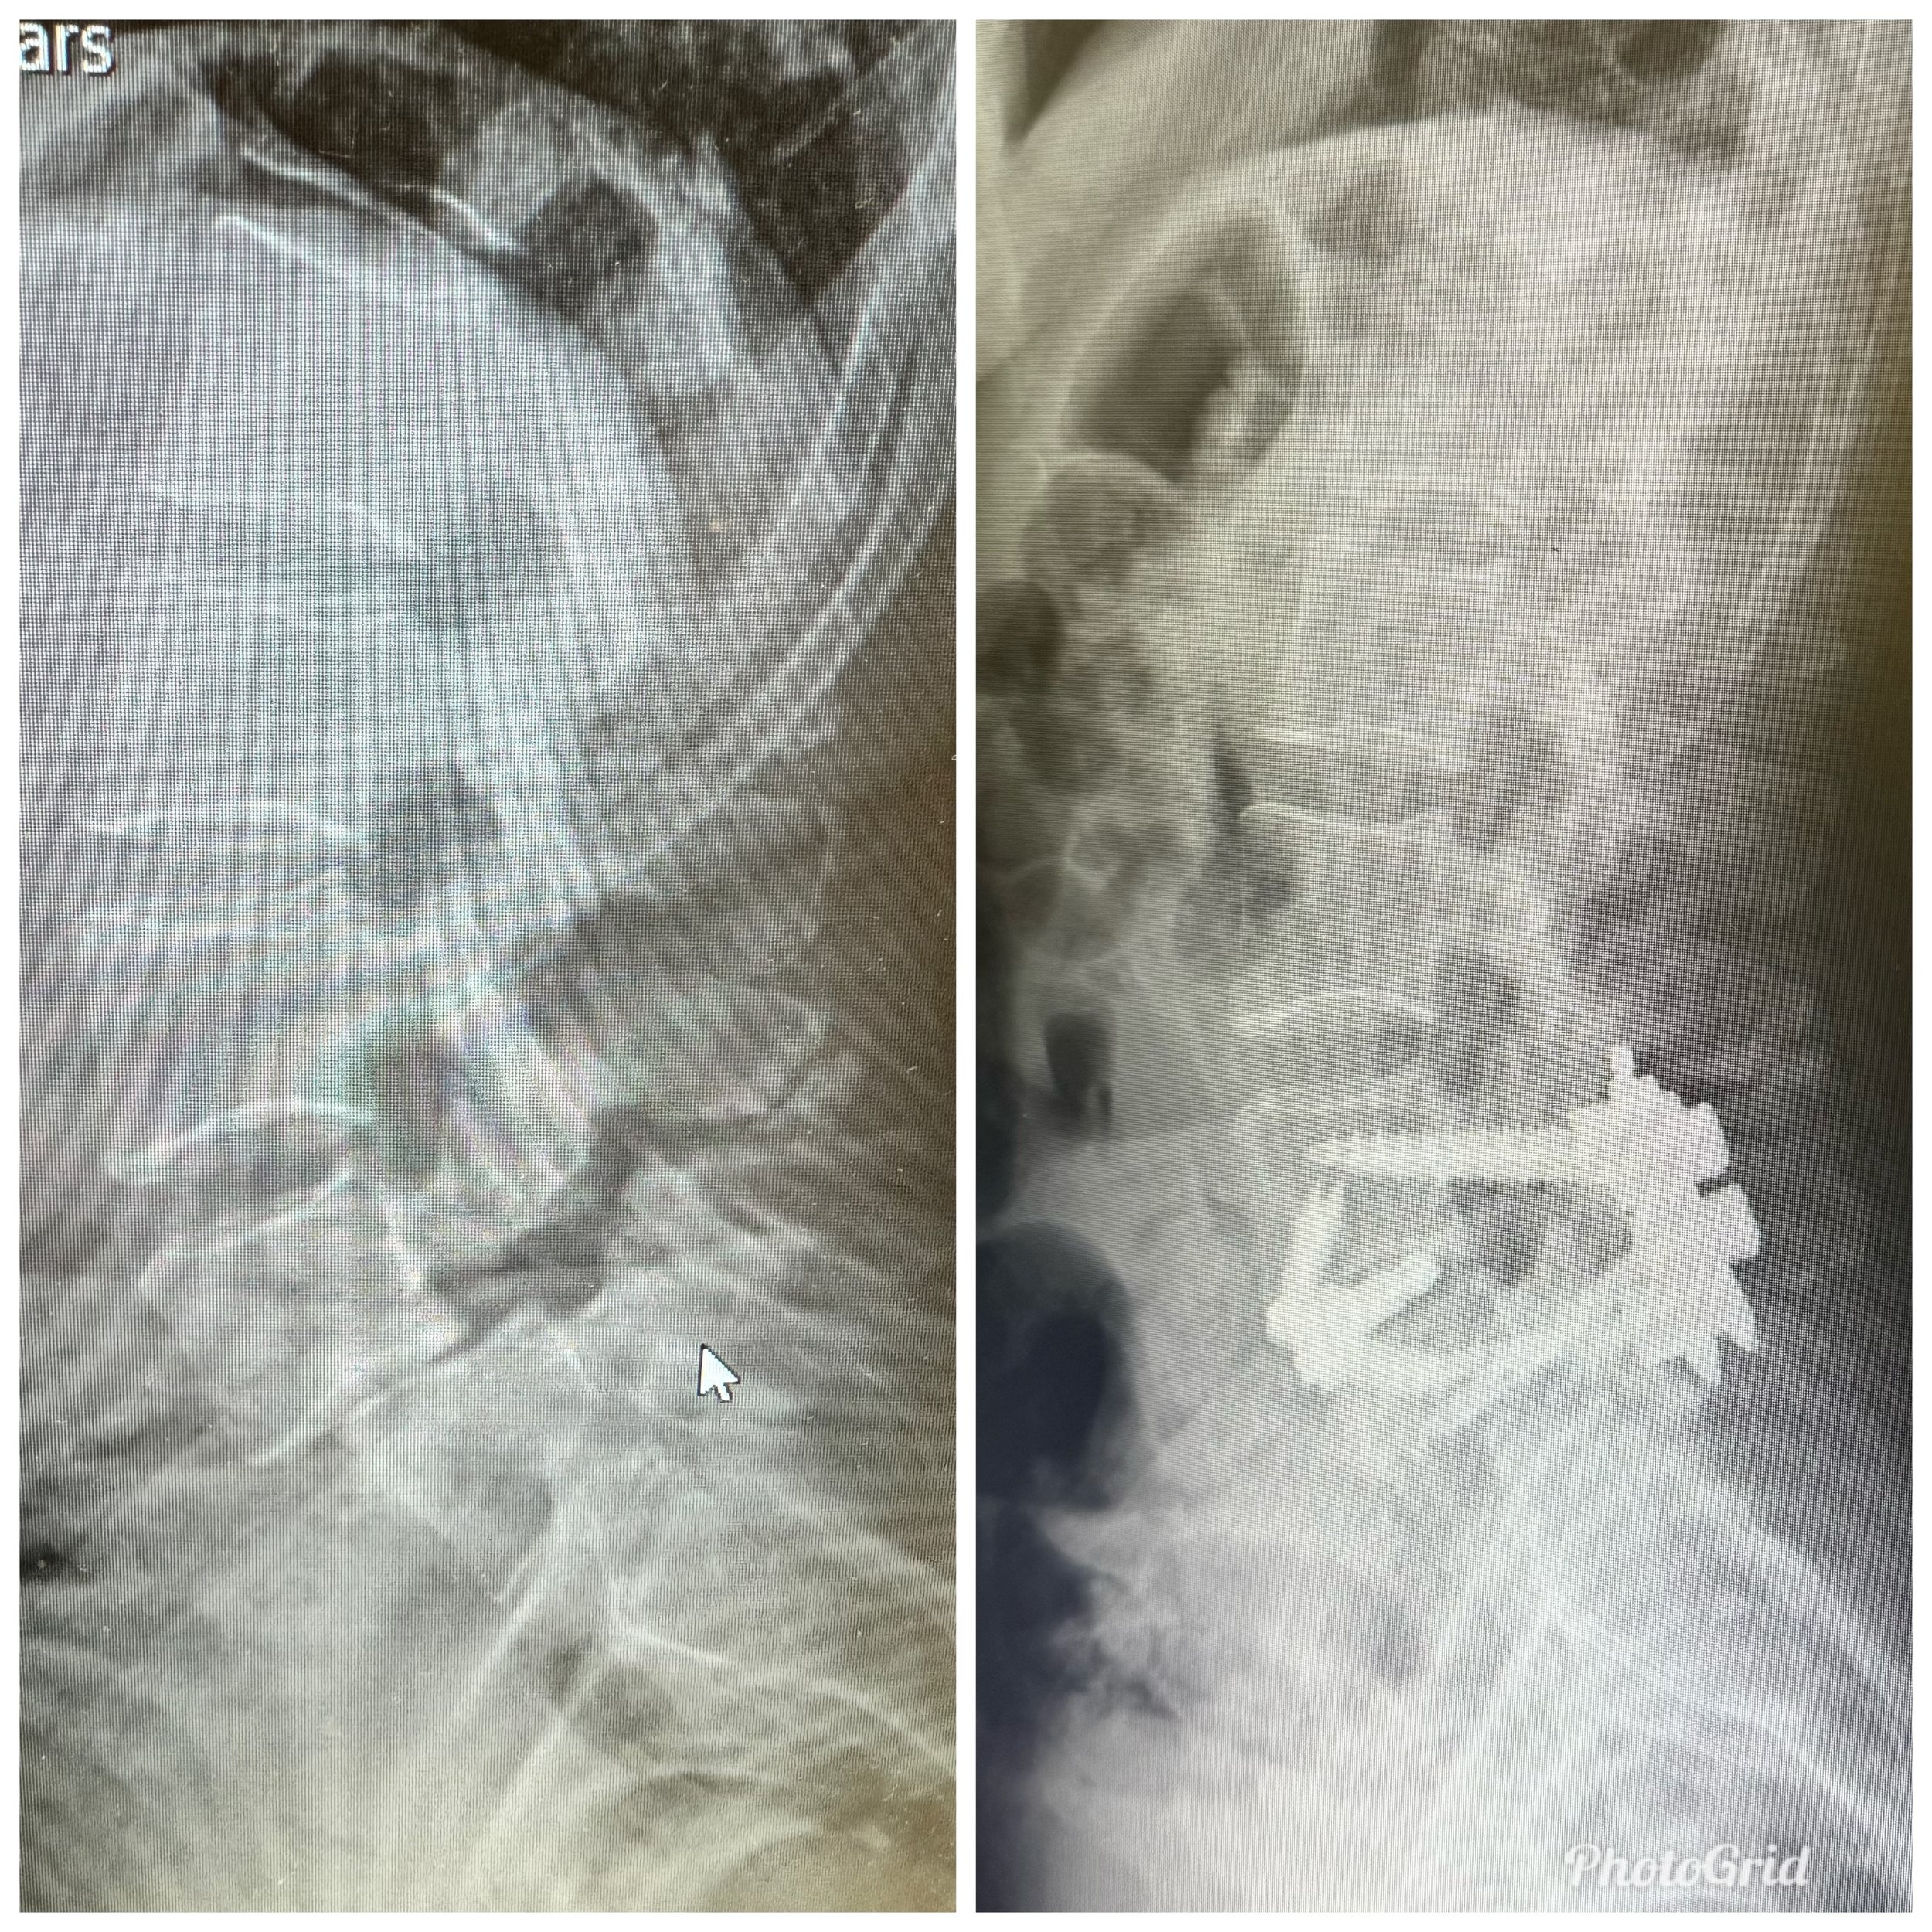

6 Days Post Op Update

I am recovering comfortably at home from my ALIF procedure on Tuesday. I haven’t been in pain, I am moving very well and I am officially an inch taller! WILD!

Into Surgery I go

I will arrive in the morning at Piedmont Hospital for my ALIF procedure and praying all goes smoothly. My family and friends have been incredibly supportive. Here I go!

Back to Adventure

Wasn’t expecting to follow my husband down this road, but my back issues took a turn and I have a spine surgery ahead.